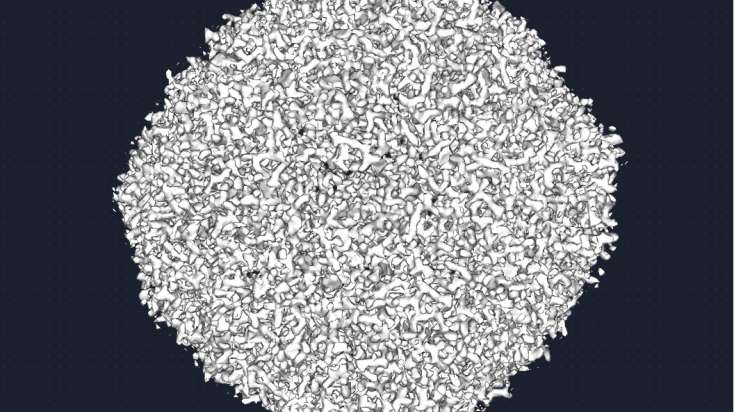

A két új krio-elektronmikroszkóp - a Tundra és a Glacios 2 - elsősorban biológiai molekulák, például fehérjék vagy mikrobák és sejtek szerkezetének vizsgálatára szolgál. A kutatók először az egyik berendezéssel ellenőrzik a minták minőségét, majd a másikkal részletes adatokat gyűjtenek, amelyekből háromdimenziós molekulamodellek készíthetők.

A krio-elektronmikroszkópia különlegessége, hogy a mintákat rendkívül gyorsan, csaknem –196 °C-ra hűtik le. Ez a módszer megakadályozza, hogy a víz jégkristályokat képezzen, így a biomolekulák eredeti szerkezete változatlan marad.

„Olyan, mintha lefagyasztanánk egy pillanatot az életből. A molekulák abban az állapotban maradnak meg, ahogyan a természetben is működnek, így pontosabban megérthetjük a működésüket” – magyarázta a kutató. Ez különösen fontos például vírusok vizsgálatánál. A módszerrel részletesen feltérképezhető egy vírus szerkezete, például az a fehérje, amellyel a sejtekhez kapcsolódik, ilyen kutatások segítették a tudósokat a járvány idején a COVID-19 vírusának megértésében is.